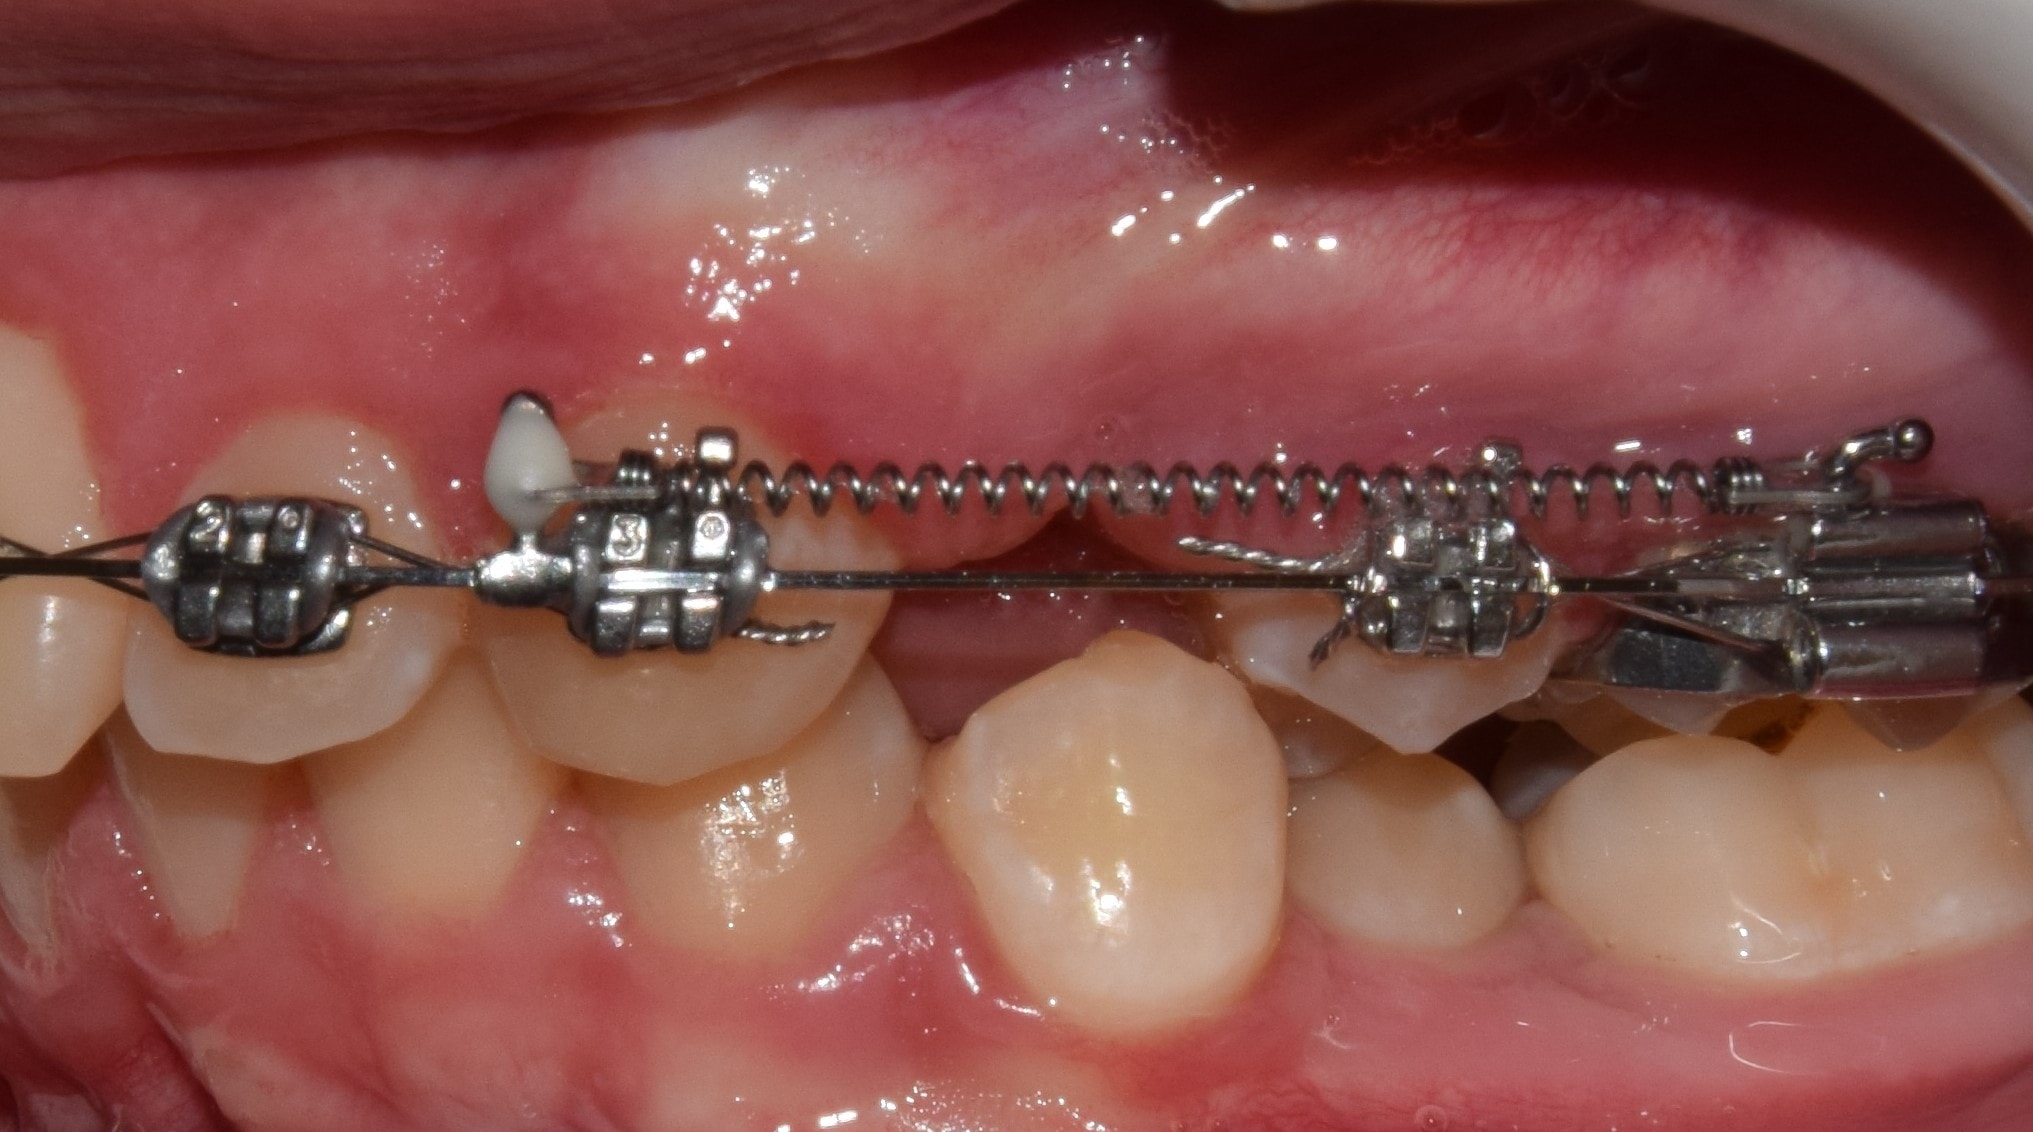

Fogszabályozási miniimplantátum

A modern fogszabályozó kezelések alappillérei a fogszabályozási miniimplantátumok. Óriási előnyökkel jár használatuk, és a kezelések sikerességét hihetetlen mértékben megnövelik. Miniimplantátumok segítségével a korábban csak műtéttel, foghúzással kezelhető pácienseket egyszerű fogszabályozással is tökéletesen kezelni tudjuk! Az önligírozó fogszabályozó rendszerek és miniimplantátumok kombinált használata talán a legsikeresebb technikát jelenti jelenleg. Nagyon minimális helyi érzéstelenítésben történik behelyezésük, mely nagyjából 20-40 másodpercet vesz igénybe! Az injekciót leszámítva teljesen fájdalommentes beavatkozás! A fogszabályozási miniimplantátumok a fogászati implantátumokkal szemben nem kerülnek szoros kapcsolatba a környező szövetekkel, ezáltal későbbi eltávolításuk igazán egyszerű, érzéstelenítő sem szükséges hozzá. Technika- és szájhigiéné érzékeny rendszerről beszélünk. Nem megfelelő fogmosás következményeként a minicsavarok meglazulhatnak, kieshetnek.

Behelyezési területük szerint három fő csoportot különböztetünk meg:

1. A gyökerek közé helyezett miniimplantátumok

Ezeket a miniimplantátumokat a fogak gyökerére merőlegesen helyezzük be, a gyökerek közé. Pontos helyzetüket előzetes kisröntgen alapján határozzuk meg. Ezekkel végezzük a foghiányok zárását, bizonyos fogak pozícióban tartását, elülső fogak felfelé/lefelé mozgatását stb.

2. A gyökereken kívül helyezett miniimplantátumok

Egyre népszerűbb technika, melynek során a minicsavarokat vagy a felső őrlőfogak melletti csonttaréjba (crista infrazygomatica), vagy az alsó őrlőfogak melletti csonttaréjba tekerjük. Előnye, hogy a foggyökereken kívüli területen rögzül a csavar, így nem akadályozza a fogak mozgatását. Segítségével teljes alsó/felső fogív előre/hátra mozgatás is végezhető.

3. A szájpadba helyezett miniimplantátumok (szintén a gyökereken kívül)

Nagy sikerrel alkalmazott, biztos, kiváló csontminőségű behelyezési terület a szájpad. A szájpad középvonalába, vagy enyhén mellé helyezzük be a minicsavarokat, amikkel a felső fogív hátra/előrevitele, és felfelé mozgatása is sikerrel végezhető. Nem kell tehát félni a miniimplantátumoktól, minden esetben nagymértékben segíthetnek minket a tökéletes végeredmény elérésében. Sikerességi rátájuk 95% körül mozog! Akkor is ismertetem használatukat, ha nem biztos, hogy szükség lesz rájuk, hiszen biztosra megyünk és tökéletes mosolyt és harapást szeretnénk.